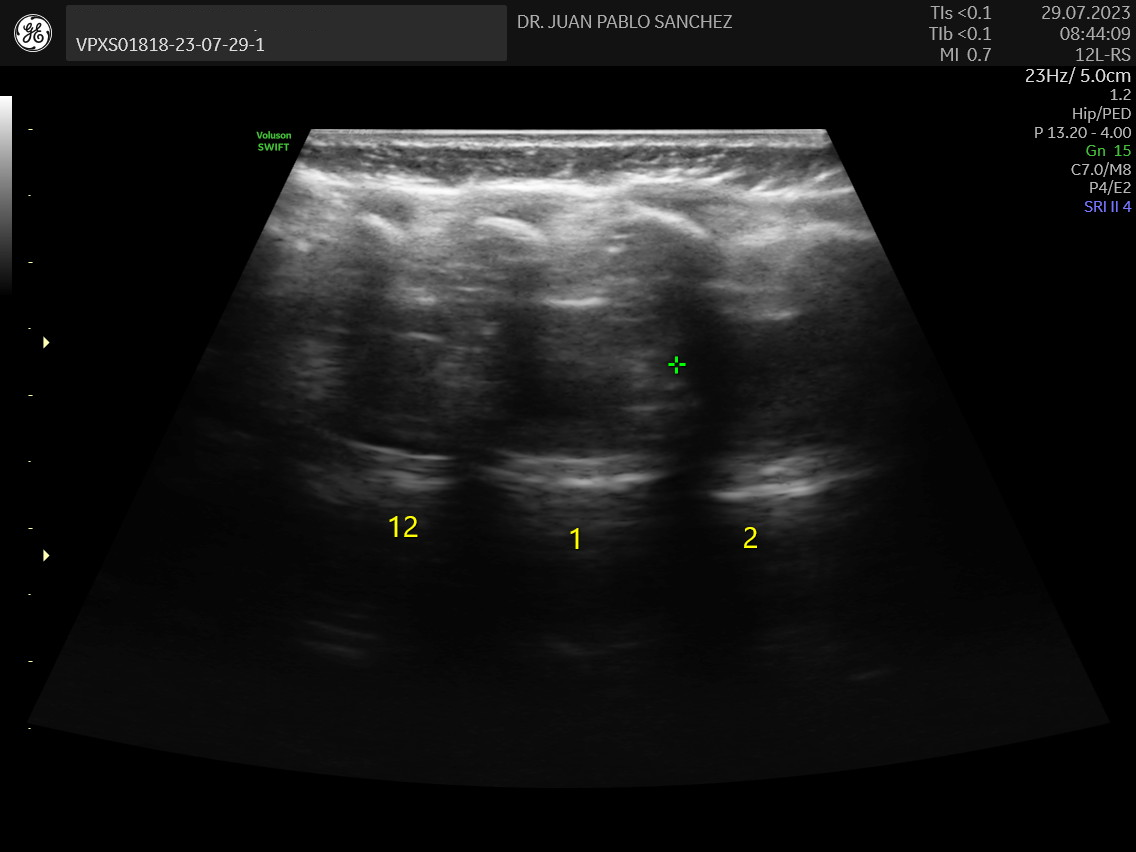

- Ecografia de caderas pediatrico